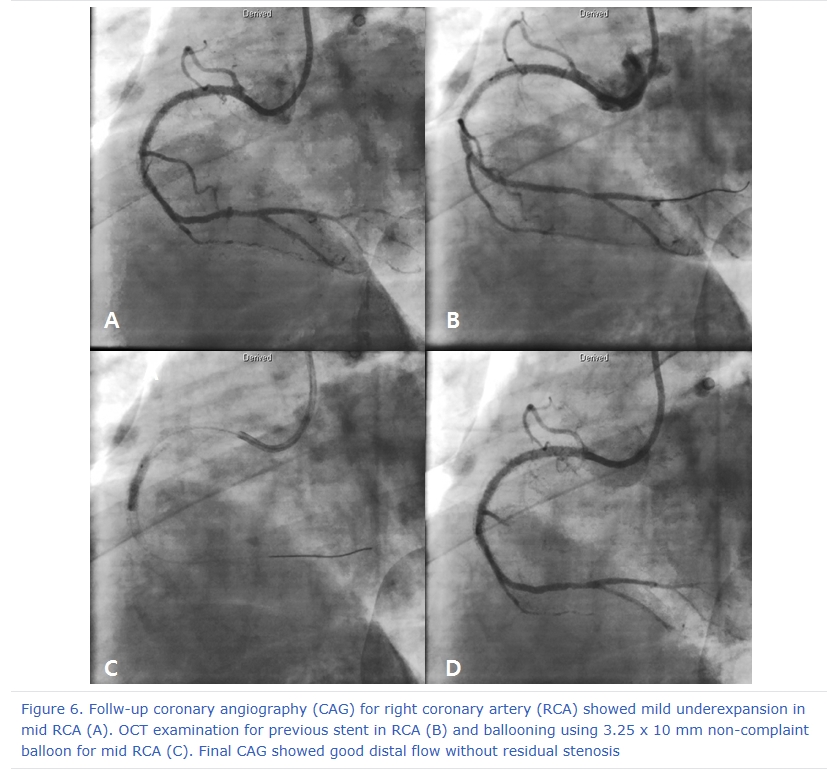

After 3 days later, we performed 2nd stage PCI for proximal LAD. CAG reveled moderate stenosis in proximal LAD (Figure 4A), so we examined optical coherence tomography (OCT) for further evaluation. It showed large amount of plaque (minimal lumen area [MLA] 2.62 mm2) (Figure 5A and 5C). We directly implanted 3.25 and 18 mm everolimus-eluting stent (Xience Alpine®), but follow-up CAG showed mild under-expansion, so we did additional ballooning using 3.25 x 10mm non-complaint balloon (Figure 4B and 4C). Follow-up OCT and CAG showed good distal flow without significant residual stenosis. (post-PCI cross sectional area [CSA] 6.65 mm2) (Figure 4D, 5B and 5D). Because of no-reflow phenomenon for RCA in previous PCI, we performed follow-up CAG and OCT for RCA. CAG and OCT showed stent underexpansion with neointima rupture and large amount of residual thrombi in mid RCA (MLA 2.39 mm2) (Figure 6A, 6B, 7A and 7C). So we did ballooning using 3.25 x 10 mm non-complaint balloon for mid RCA (Figure 6C). Follow-up CAG and OCT showed good distal flow without significant residual stenosis. (CSA 5.03 mm2) (Figure 6D, 7B and 7D). He was discharged without any complications.

Figure 6. Follw-up coronary angiography (CAG) for right coronary artery (RCA) showed mild underexpansion in mid RCA (A). OCT examination for previous stent in RCA (B) and ballooning using 3.25 x 10 mm non-complaint balloon for mid RCA (C). Final CAG showed good distal flow without residual stenosis